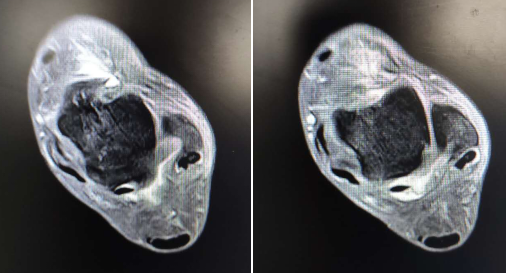

没想到,2个月后仍然疼痛,一走路就容易崴脚。忍无可忍之下,冯大姐来到betway在线登陆足踝科治疗。 徐明亮主任是周三上午坐诊,听完冯大姐的描述,经检查,发现是冯大姐足踝处的韧带出了问题。冯大姐2个月前那一次伤得不轻,核磁共振检查发现,她左外踝的距腓前韧带已经损伤断裂,左内踝三角韧带损伤,想要恢复活动能力,必须做韧带修复重建手术。

踝关节解剖结构复杂,疾病多种多样。踝关节镜是近年来兴起的一种踝关节疾病和创伤的微创治疗技术,通过2个0.5cm切口,将镜子伸到踝关节一个切口内,等于把术者的眼睛延伸到了患者体内;另外一个切口伸入特制器械来进行操作,大大减少了开放手术带来的创伤和并发症。随着器械的发展和人们对疾病的深入认识,踝关节镜的适应症越来越广泛。